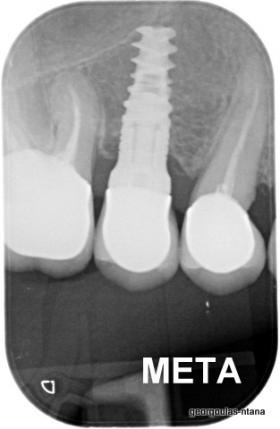

Η ασθενής ήταν δυσαρεστημένη από την εμφάνιση των άνω δοντιών της. Ήθελε τα δόντια της να αποκτήσουν ομοιόμορφο, πιο λευκό χρώμα κ να αποκτήσει ένα πιο αρμονικό χαμόγελο με φυσική εμφάνιση. Λόγω των εκτεταμένων εμφράξεων σύνθετης ρητίνης στα πρόσθια δόντια, των εμφράξεων αμαλγάματος στα πίσω αριστερά δόντια αλλά και της υπάρχουσας γέφυρας στα πίσω δεξιά δόντια, και σε συνδυασμό με την επιθυμία της ασθενούς για φυσικό αποτέλεσμα αποφασίστηκε η τοποθέτηση ολοκεραμικών στεφανών στα δόντια της άνω γνάθου. Στη θέση του δεύτερου προγομφίου δεξιά τοποθετήθηκε εμφύτευμα. Πραγματοποιήθηκε περιοδοντική θεραπεία, ενδοδοντικές θεραπείες (απονευρώσεις) κ τοποθετήθηκαν ενδορριζικοί άξονες υαλονημάτων όπου κρίθηκε απαραίτητο. Σε όλη τη διάρκεια της θεραπείας η ασθενής ήταν καλυμμένη αισθητικά κ λειτουργικά με προσωρινές αποκαταστάσεις.